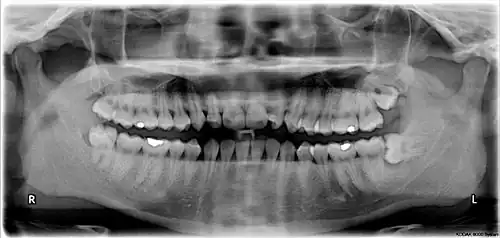

Dental x-ray of impacted lower left wisdom tooth with a horizontal orientation

Impacted wisdom teeth are classified by the direction and depth of impaction, the amount of available space for tooth eruption and the amount of soft tissue or bone that covers them. The classification structure allows clinicians to estimate the probabilities of impaction, infections and complications associated with wisdom teeth removal.[31] Wisdom teeth are also classified by the presence of symptoms and disease.[32]

The upper left (picture right) and upper right (picture left) wisdom teeth are distoangularly impacted. The lower left wisdom tooth is horizontally impacted. The lower right wisdom tooth is vertically impacted (unidentifiable in orthopantomogram).